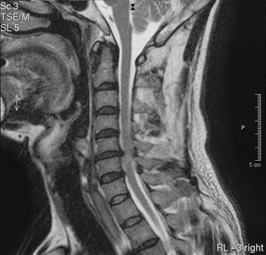

臨床応用例 |